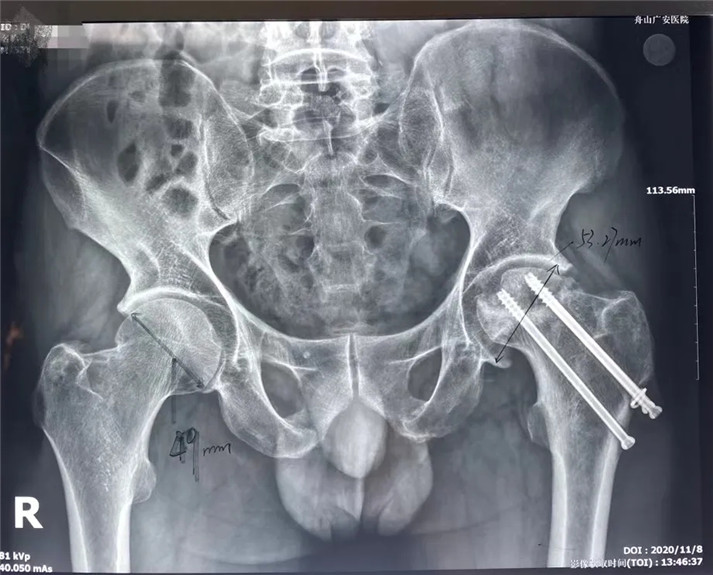

62歲的丁大哥從老家安徽至舟山打工已經(jīng)10多年了。和眾多民工兄弟一樣,丁大哥上有老、下有小,生活的重?fù)?dān)壓得他一絲都不敢懈怠。雖然清苦,日子倒也平靜。然后,一次意外,卻讓原本就困難的家庭雪上加霜。今年3月份,丁大哥在家干活時(shí)意外摔到左腿,去醫(yī)院診斷為左股骨脛骨折,并在他院進(jìn)行了骨折內(nèi)固定手術(shù)。因?yàn)榻?jīng)濟(jì)原因,術(shù)后沒(méi)多久,丁大哥就下地干活了,導(dǎo)致了股骨頭壞死。當(dāng)時(shí),醫(yī)生勸他做手術(shù)。丁大哥害怕手術(shù)費(fèi)用大,家庭難以承受,便選擇了回家休養(yǎng)。前段時(shí)間,左腿實(shí)在疼痛難忍,甚至無(wú)法走路。經(jīng)多方打聽(tīng)到我院對(duì)于治療該種疾病很有經(jīng)驗(yàn),丁大哥來(lái)到了羅軍主任門(mén)診。

結(jié)合影像學(xué)表現(xiàn)研究后,骨科中心羅軍主任診斷丁先生為左股骨頭壞死,并建議其行全髖關(guān)節(jié)置換手術(shù)。

術(shù)前

考慮到患者的年齡、骨折類(lèi)型等情況,以及患者的種種擔(dān)憂(yōu),為精準(zhǔn)治療、加快愈合、避免關(guān)節(jié)脫位及肢體長(zhǎng)短不等,羅軍主任團(tuán)隊(duì)采用了近期引進(jìn)的AI HIP置換術(shù)前規(guī)劃系統(tǒng)為患者行術(shù)前規(guī)劃。他們將丁先生的術(shù)前CT數(shù)據(jù)導(dǎo)入到系統(tǒng)中,通過(guò)自動(dòng)識(shí)別骨盆和股骨建立了計(jì)算機(jī)數(shù)字三維模型。AI HIP顯示患者適合使用合適的髖臼杯、股骨柄、標(biāo)準(zhǔn)陶瓷球頭、陶瓷內(nèi)襯,并精準(zhǔn)定位了截骨線(xiàn),可以有效幫助醫(yī)生在手術(shù)中做到精確截骨。

AI HIP術(shù)前規(guī)劃